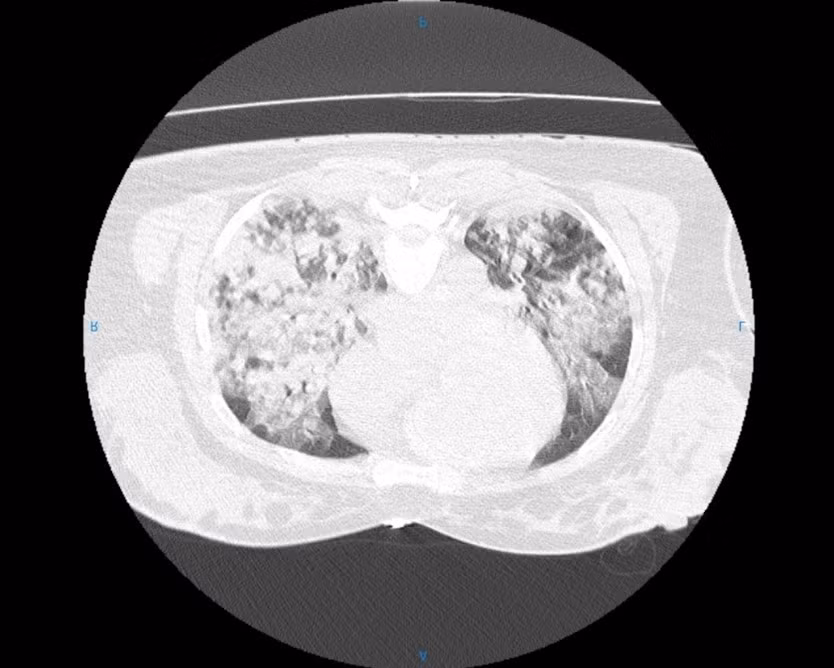

Ngay lập tức, các bác sĩ phải đặt ống nội khí quản và tiến hành hồi sức khẩn cấp. Chụp CT ngực ghi nhận tổn thương lan tỏa hai phổi, phù hợp tình trạng tổn thương phổi cấp sau đuối nước.

Trong 72 giờ đầu, diễn biến hô hấp của bệnh nhân trở nặng. Tại Khoa Hồi sức Tích cực - Chống độc - Thận nhân tạo, bệnh nhân được an thần, thở máy và điều trị kháng sinh. Sang ngày thứ 3, oxy máu tiếp tục giảm, hình ảnh CLVT (Chụp Cắt Lớp Vi Tính - CT scan) phổi cho thấy tổn thương lan rộng, nghi ngờ hội chứng suy hô hấp cấp tiến triển (ARDS).

Hình ảnh tổn thương phổi của bệnh nhân/Ảnh Bệnh viện Đa khoa Cẩm Phả.